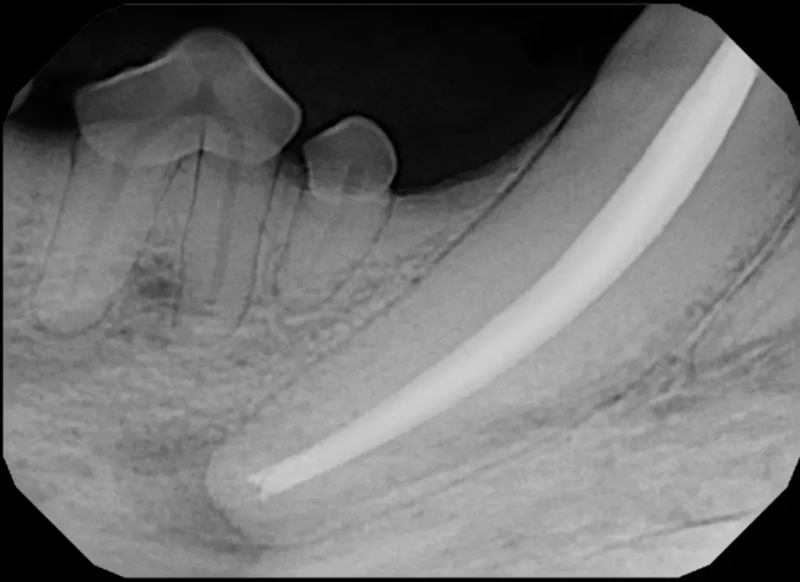

Surgical Extraction of Diseased Teeth

Periodontal disease is extremely common in dogs and cats. Over 80% of dogs and cats over two years of age have some degree of periodontal disease. Periodontal disease is best prevented by yearly professional dental cleanings starting at two years of age and at home brushing at least three times weekly. Brushing should begin at a very early age to allow your new pet to get used to regular brushing. In severe cases of infection or periodontal disease, the teeth may need to be surgically extracted. Extractions should always involve x-rays of the tooth first, as many teeth have multiple roots or may be diseased below where the eye can see. Extracting larger teeth in animals requires oral surgery, equivalent to removing wisdom teeth in people. It is vital that all of the tooth and roots be removed for the periodontal infection to resolve. In cases of important teeth with mild to moderate periodontal disease, multiple periodontal treatments can be offered to help save these teeth.

Challenging Extractions

Sometimes teeth can be quite a challenge to remove. We routinely perform difficult extractions due to abnormally formed teeth, impacted teeth, extractions from weakened bone, and retained roots, Sometimes during a routine extraction a root can get pushed into the mandibular canal or the nasal cavity, and if that happens, we are here to get it out!